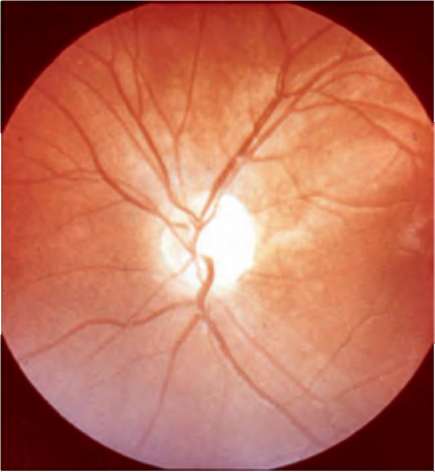

Рис. 12.1. Глазное дно. Норма